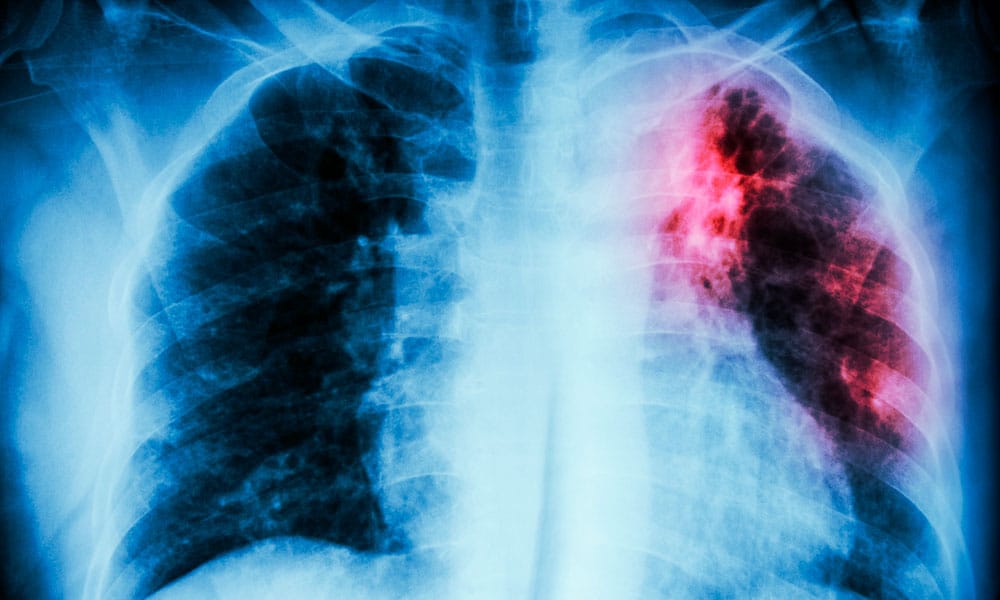

Se trata de una enfermedad contagiosa que lacera pulmones y es transmitida por aire cuando una persona infectada tose, habla o estornudar. Es curable, refiere el Departamento de Salud, pero requiere de ser constante en los tratamientos.